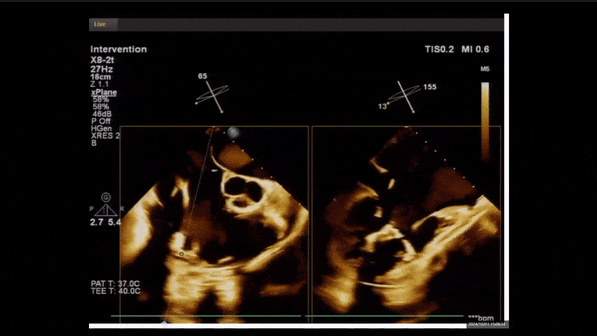

術前TEE評估

1、3D TEE顯示雙房及右室擴大,右室中段直徑40mm,右室FCA 52%。三尖瓣環TAPSE 22mm,三尖瓣環左右徑49mm,三尖瓣隔葉長度16mm,前葉長度21mm,后葉長度34mm,三尖瓣前隔gap 11mm,后隔gap 5.6mm,AP gap 12mm,診斷極重度功能性三尖瓣返流(Type I型三尖瓣:Torrential FTR 5+)。

2、彩色多普勒顯示:收縮期三尖瓣口返流束起源于后隔交界、前后葉之間及前隔交界,返流束縮流頸最大寬度27mm,三尖瓣返流口EOA=2.02cm2,返流容積124ml,收縮期三尖瓣返流峰值速度2.64m/s,返流峰值壓差28mmHg,PAPs 43mmHg,舒張期三尖瓣口平均跨瓣壓差1mmHg,肝左靜脈可見明顯逆向血流波。

術中經食道超聲輔助下可見LuX-Valve Plus夾持件抓捕瓣葉狀態良好,夾持件在位,室間隔錨定位置良好,假體瓣膜整體錨定狀態穩固。

術后即刻經食道超聲可見,三尖瓣假體瓣膜位置合適,牛心包瓣葉運動狀態良好,開閉正常,瓣周及瓣葉對合緣處未見明顯返流,心電圖及心包狀態較術前無明顯變化。